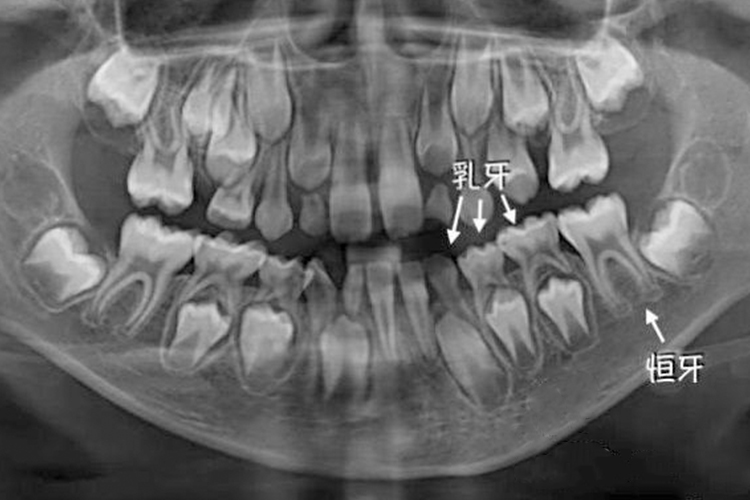

儿童牙齿X线可看到有两套牙齿,即乳牙和恒牙。当牙齿萌出时,儿童可伴有发热、唾液增多等现象,同时注意牙齿保健。

儿童时期的牙齿主要是乳牙和年轻恒牙。每个牙齿的发育时间虽然不尽相同,但是都是经过生长期、钙化期和萌出期3个阶段,通过X光可以看到乳牙根分叉度大,牙根有生理性吸收,在其下方还有一正在发育的继承恒牙。同时会伴有唾液增多、流涎、食欲减退、牙龈疼痛等症状。